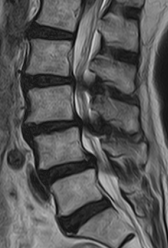

術前MRIでは腰椎椎間板ヘルニアを認め、神経の圧迫を認めています。後方からのヘルニア摘出術により神経症状は劇的に改善しました。

術前MRIでは脊柱管の狭窄を認め、神経の圧迫を認めています。後方からの除圧術後、神経への圧迫は改善しています。